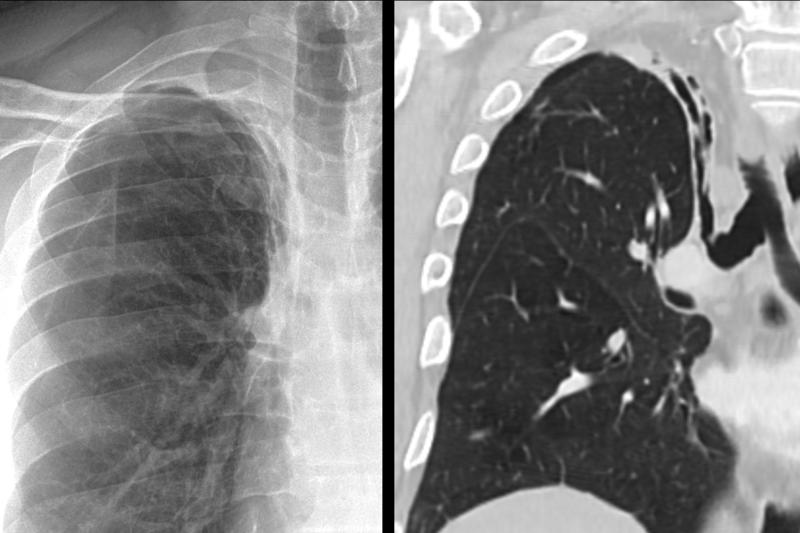

Gallery Lobar Collapse RUL Collapse RUL collapse Case 11

RUL collapse Case 11